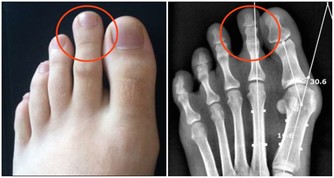

尿液中鈣、草酸、尿酸排出量增加。長期臥床,甲狀旁腺機能亢進(再吸收性高尿鈣症),特發性高尿鈣症(吸收性高尿鈣症一腸道吸收鈣增多或腎性高尿鈣症-腎小管再吸收鈣減少),其他代謝異常及腎小管酸中毒等,均使尿鈣排出增加。痛風,尿持續酸性,慢性腹瀉及噻嗪類利尿劑均使尿酸排出增加。內源性合成草酸增加或腸道吸收草酸增加,可引起高草酸尿症。

大多數草酸鈣結石原因不明。磷酸鈣和磷酸鎂銨結石與感染和梗阻有關。尿酸結石與痛風等有關。胱氨酸結石是罕見的家族性遺傳性疾病,因尿中排出大量胱氨酸所致。